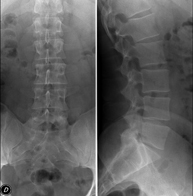

Tècnica que usa els raigs X a través de la qual s'obtenen imatges de l'abdomen (estómac, intestí prim, intestí gros, fetge, ronyons, bufeta, pelvis òssia, etc.) per al seu estudi. - RX Columna lumbar

Tècnica que usa els raigs X a través de la qual s'obtenen imatges de la columna lumbar per al seu estudi. - TEGD (trànsit esòfag-gastro-duodenal)

Tècnica que usa els raigs X a través de la qual s'obtenen imatges de la columna dorsal per al seu estudi. Indicacions: traumatisme, mal d'esquena. - RX Columna lumbar

Tècnica que usa els raigs X a través de la qual s'obtenen imatges de la columna lumbar per al seu estudi. Indicacions: ciàtica, traumatisme, dolor lumbar. - RX Sacre-còccix